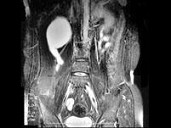

- 多项选择题女,31岁, 右侧腰部胀痛不适,MRI检查如图所示, 下列说法正确的是 ( )

A、右肾重度积水

B、右侧输尿管粗细不均并迂曲扩张

C、右侧输尿管下段呈囊样扩张

D、左肾输尿管未见异常

E、考虑为右侧输尿管囊肿